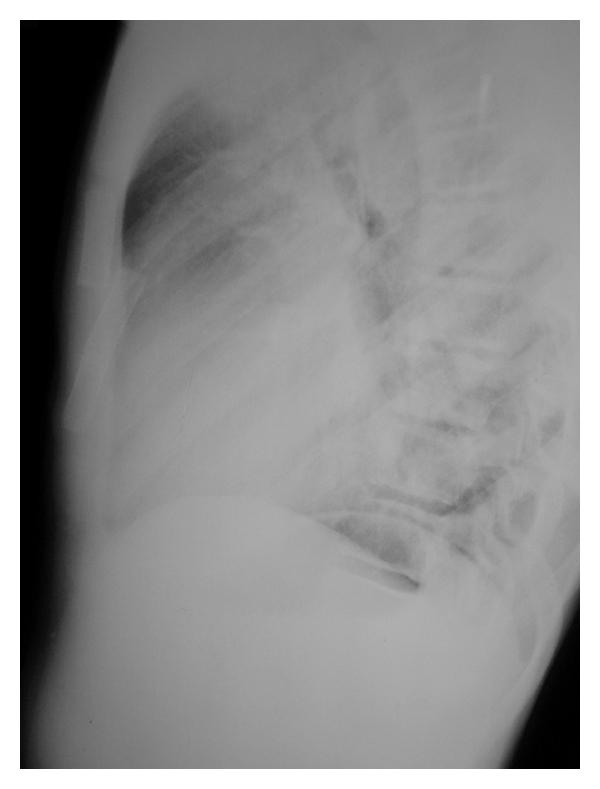

Trauma may lead to sternal fracture or dislocation. Dislocation of a sternal segment in the childhood period is very rare as for sternal fractures in children. There are only six case reports regarding the issue in the literature. Additionally, there is not an established consensus for the treatment of the pathology. In this paper we present traumatic dislocation of a sternal body segment in a 10-year-old child who was successfully managed conservatively by closed reduction together with the review of the literature. Surgical treatment is not necessary especially in acute cases. Pathology may be treated with closed reduction. Callus formation usually supports the dislocated part of the sternum in time.